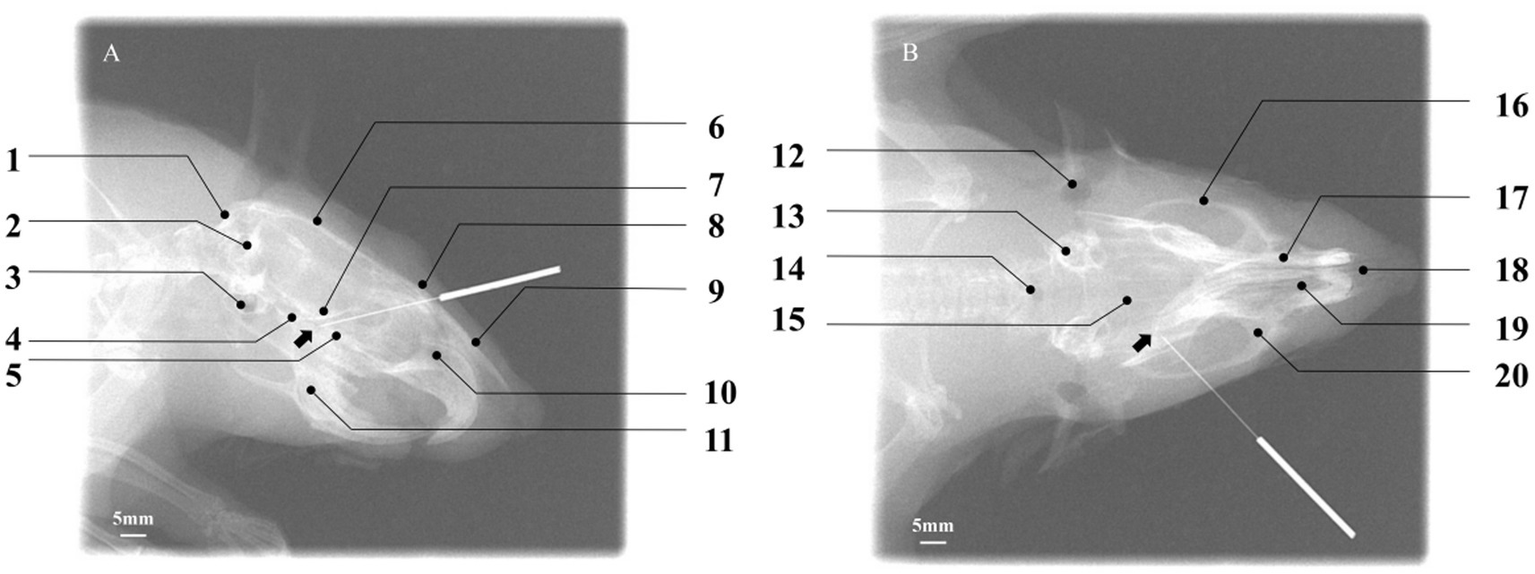

To objectively verify whether the needle tip (NT) accurately reached the PPF region, digital X-ray fluoroscopy was performed on six rats in the acupuncture group for image acquisition and spatial analysis. In the lateral radiograph (Figure 6A), the needle tip was ultimately located within a triangular radiolucent area bounded ventrally by the basisphenoid bone, posteriorly by the maxilla, and dorsally by the perpendicular plate of the palatine bone. This area corresponds precisely to the core projection zone of the PPF in the lateral view. In the coronal radiograph (Figure 6B), the needle tip was clearly observed within a narrow space located lateral to the nasal cavity, medial to the body of the maxilla, and superior to the horizontal plate of the palatine bone. This space is bounded dorsally by the region extending from the inferior orbital fissure and ventrally by the hard palate (formed by the palatine process of the maxilla and the horizontal plate of the palatine bone), accurately corresponding to the anatomical position of the PPF in the coronal plane. The radiographic results confirmed that all needle tips successfully and consistently reached the target area in the PPF, thereby validating the accuracy and reproducibility of the present acupuncture pathway.

Verification of acupuncture needle placement within the pterygopalatine fossa using digital X-ray fluoroscopy. (A) Lateral view: the needle tip (NT) is positioned within the target PPF region, with the black arrow indicating the location of the sphenopalatine foramen. Key cranial landmarks are annotated: (1) occipital bone; (2) foramen magnum; (3) auditory structures/otic region; (4) basisphenoid bone; (5) palatine bone; (6) parietal bone; (7) presphenoid bone; (8) frontal bone; (9) nasal bone; (10) nasal cavity; (11) mandible. Scale bar: 5 mm. (B) Coronal view: the NT is located within the target PPF, with the black arrow indicating the sphenopalatine foramen. Annotated cranial landmarks include: (12) external auditory meatus; (13) internal ear; (14) foramen magnum; (15) parietal bone; (16) zygomatic bone; (17) nasal bone; (18) nasal septum; (19) nasal cavity; (20) maxilla. Scale bar: 5 mm. The successful placement, as defined by its spatial relationship to surrounding cranial landmarks, confirms the accuracy of the established acupuncture pathway.